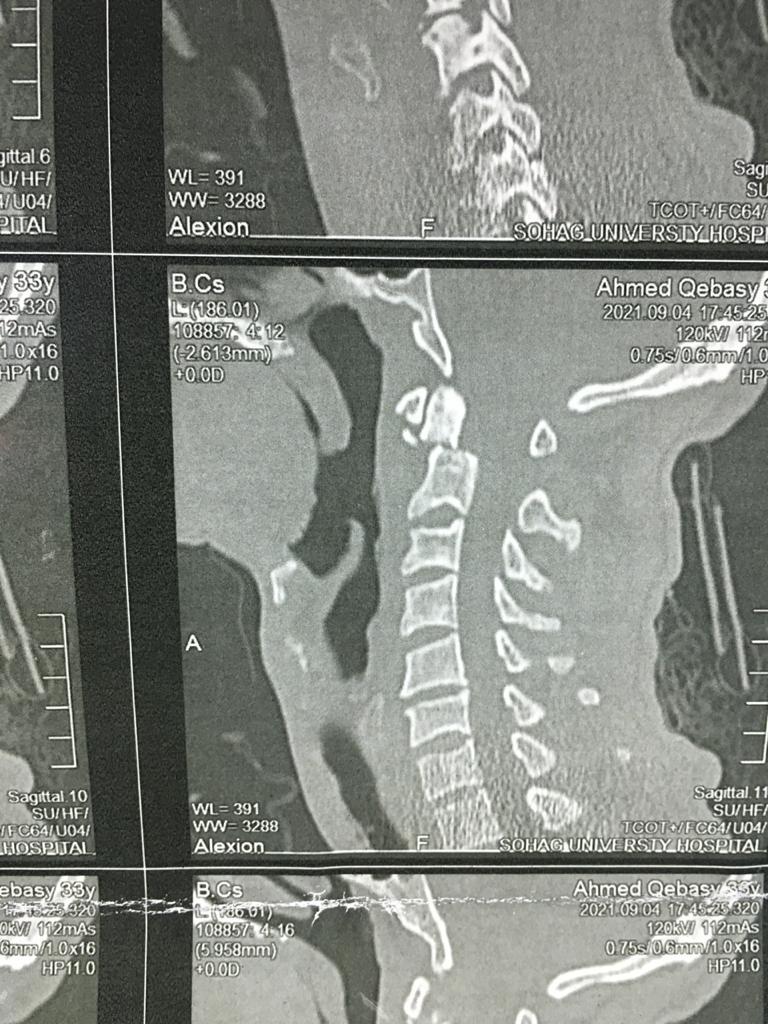

وأوضح الدكتور حمدي سعد مدير المستشفى الجامعي أنه بعد إجراء الفحوصات والإشاعات اللازمة للمريض تبين وجود كسر في الفقرة الثانية من العمود الفقري الرقبي، ويحتاج إلى جراحة عاجلة لتثبيت الفقرة العنقية، حيث كان هذا الكسر يشكل خطرًا كبيرًا على النخاع الشوكي وحياة المريض.

وذكر الدكتور عبدالرحمن الشيخ رئيس قسم جراحة العظام أنه بعد دراسة الحالة في ضوء نتائج الفحوصات الطبية، تم اتخاذ كافة التدابير التحضيرية للعملية، لافتًا الي ان الفريق الطبي الذي إجري العملية الجراحية للمريض كان تحت إشراف الدكتور أحمد صالح أستاذ جراحة العظام والعمود الفقري، حيث تم تثبيت الكسر بنجاح، وبدأ المريض الحركة بحرية تامة بمفرده بدون اي وسائل مساعدة.